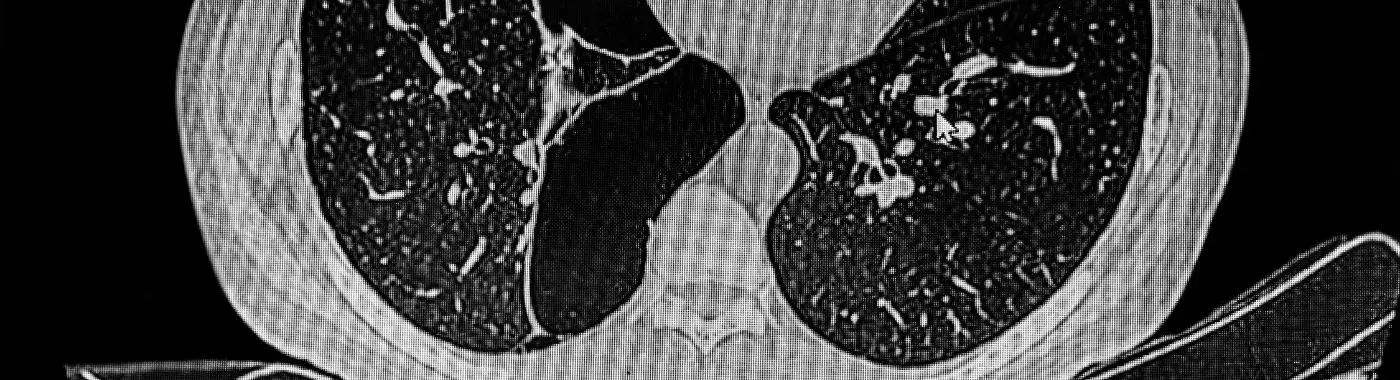

• Imaging Studies: Chest X-rays and CT scans can reveal the presence of bullae and assess the extent of lung damage.

Bullous emphysema is a subtype of emphysema, a progressive lung disease that falls under the umbrella of chronic obstructive pulmonary disease (COPD). In bullous emphysema, the alveoli become damaged and lose their elasticity, leading to the formation of large, abnormal air spaces (bullae) within the lungs. These bullae can occupy significant portions of lung tissue, reducing the surface area available for gas exchange and making it difficult for individuals to breathe. This condition is often associated with long-term smoking, but it can also occur in non-smokers due to other factors.

Bullous emphysema is a specific form of emphysema, a chronic lung condition that affects the air sacs (alveoli) in the lungs. This condition is characterized by the formation of large air-filled spaces, known as bullae, which can significantly impair lung function. Understanding bullous emphysema is crucial, as it can lead to serious health complications if left untreated. This article aims to provide a comprehensive overview of bullous emphysema, including its causes, symptoms, diagnosis, treatment options, and more.